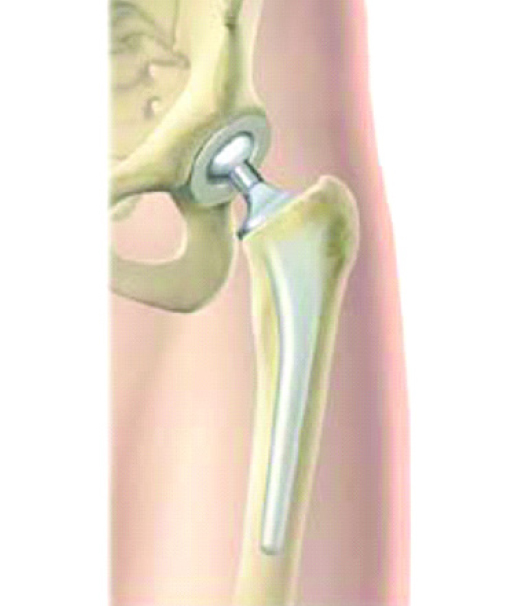

This is a total hip replacement

This is a partial hip replacement

If the fracture is in the neck of the femur, the blood supply to the head of the femur will be compromised, and a partial or total hip replacement will be necessary.